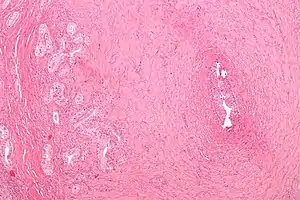

| Micrograph of vasitis nodosa (left of image). H&E stain. | |

Vasitis nodosa is a complication experienced in approximately 66% of men who undergo vasectomy.[1] It is a benign nodular thickening of the vas deferens, in which small offshoots proliferate, infiltrating surrounding tissue.[2] It can be mistaken for low-grade adenocarcinoma by pathologists,[3] and is implicated in late vasectomy failure.[2]